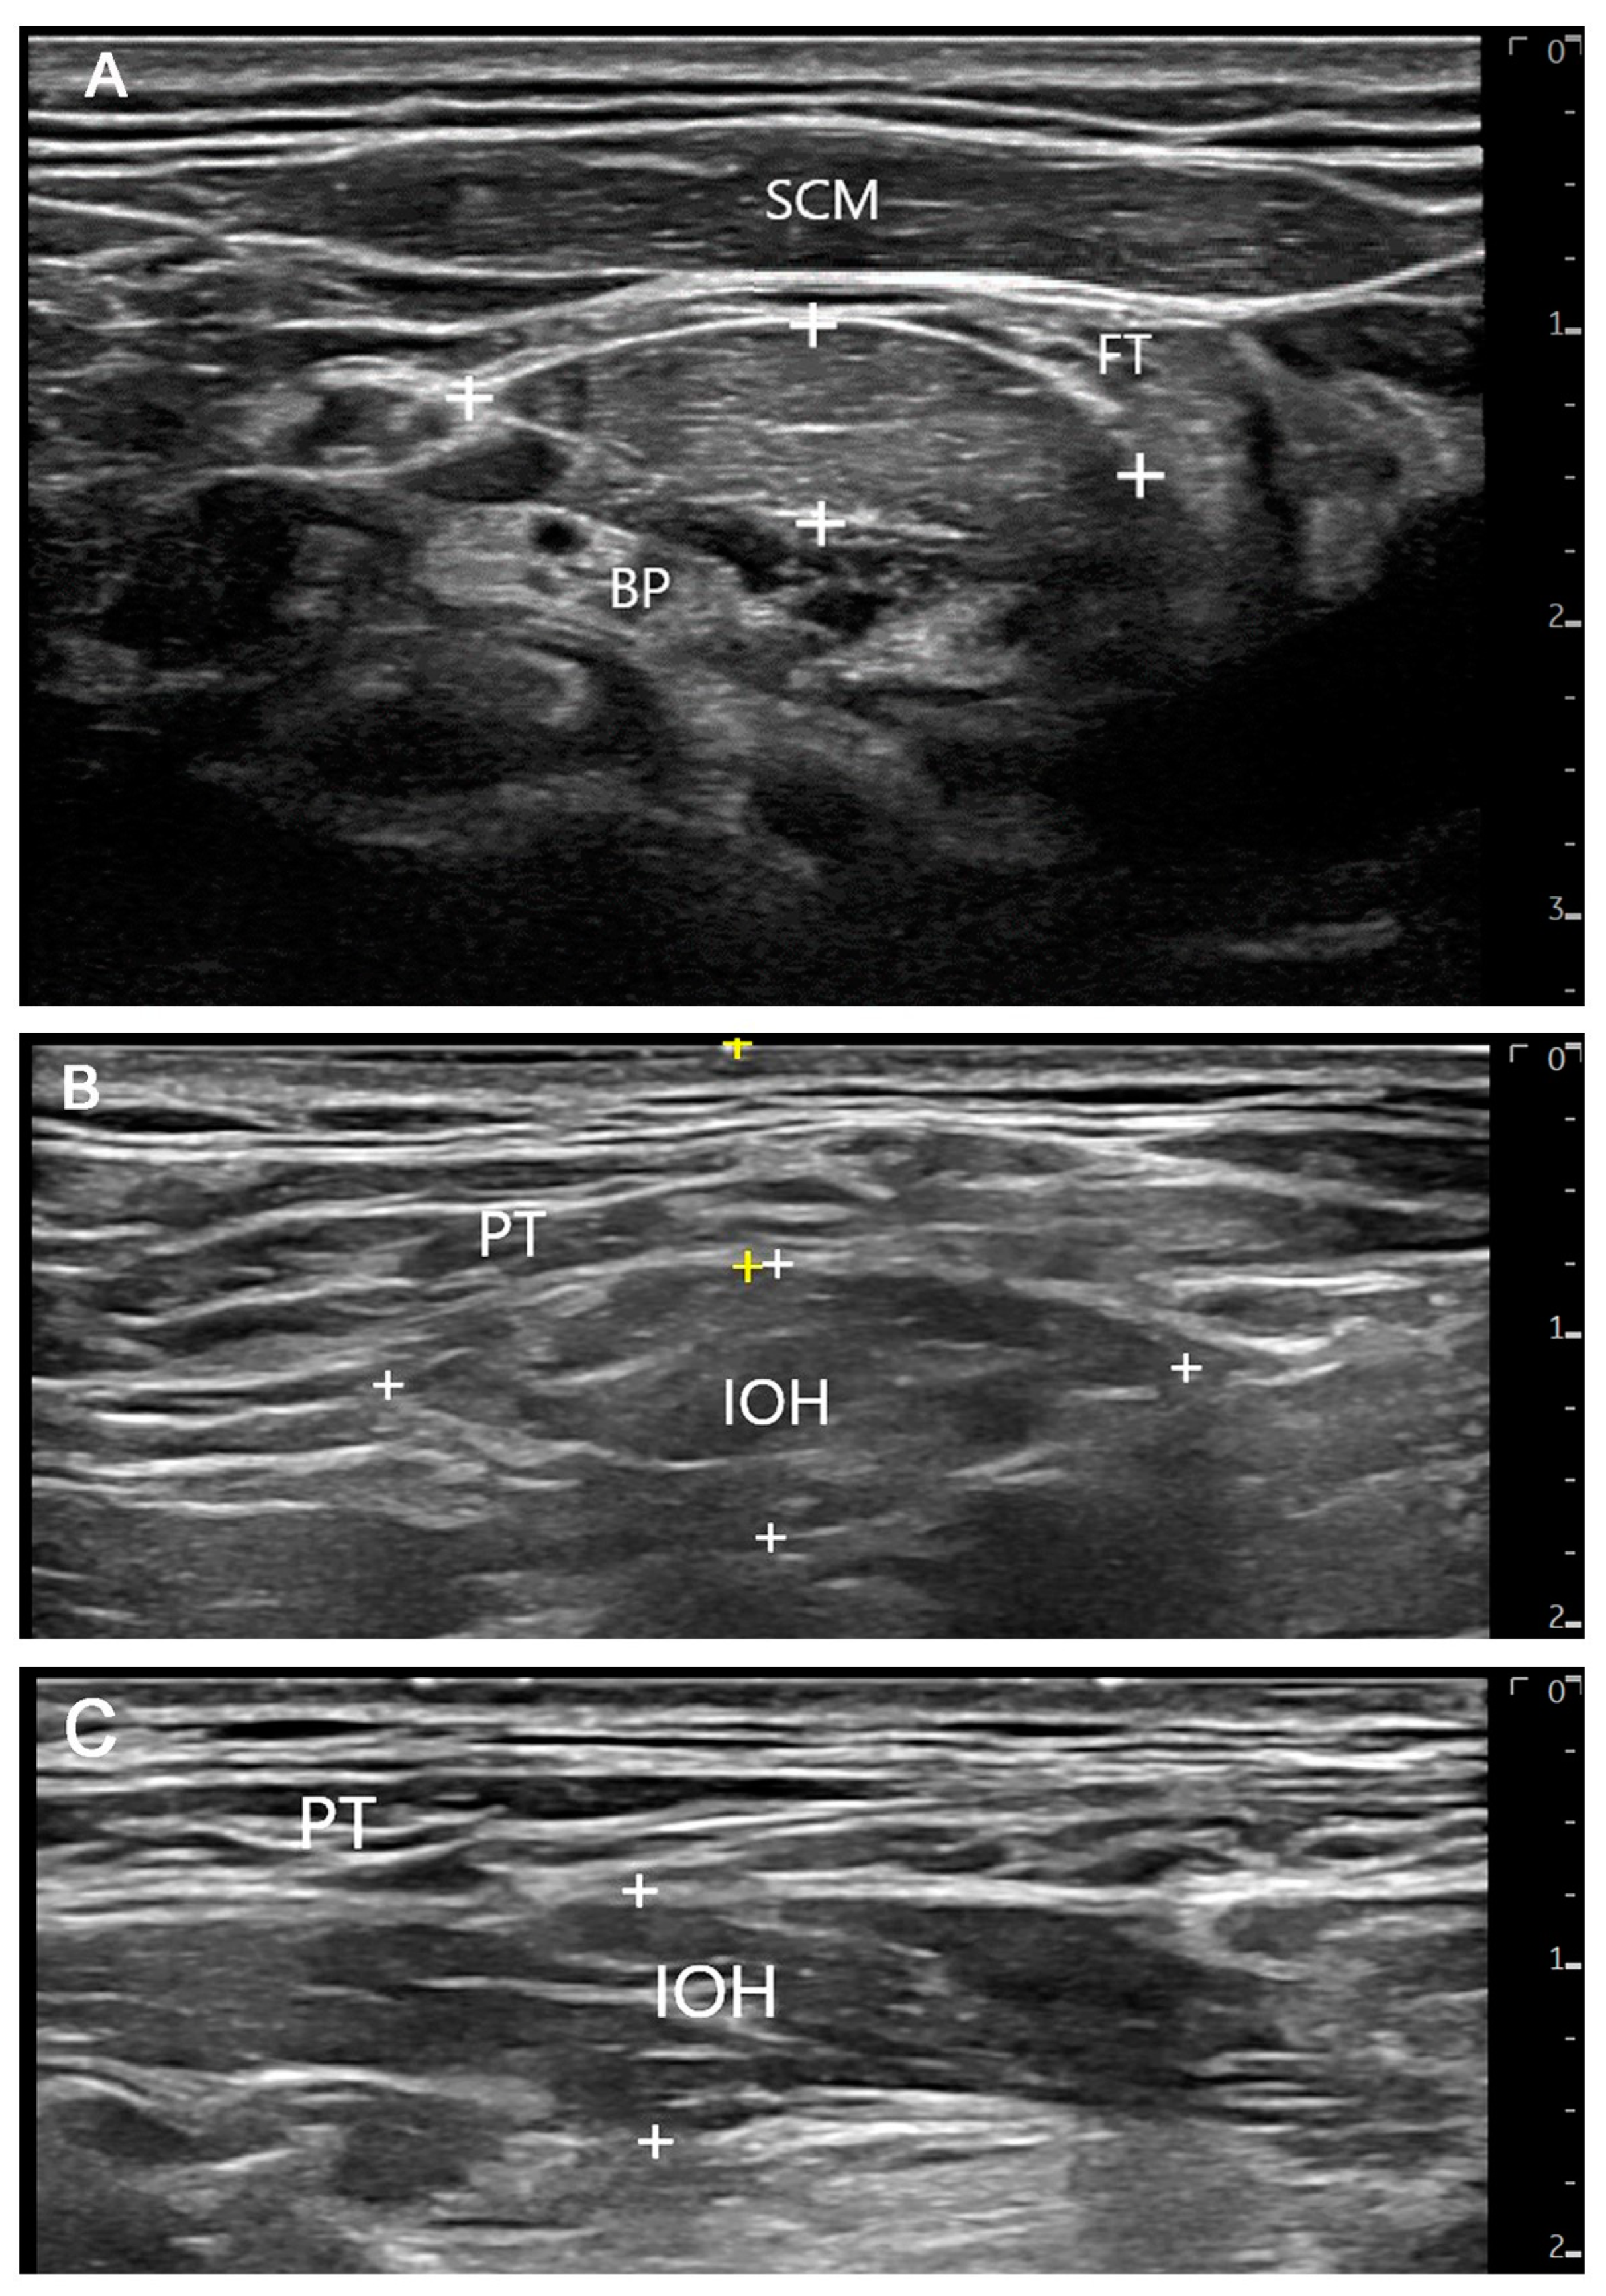

3.2.2. Ultrasonographic Findings